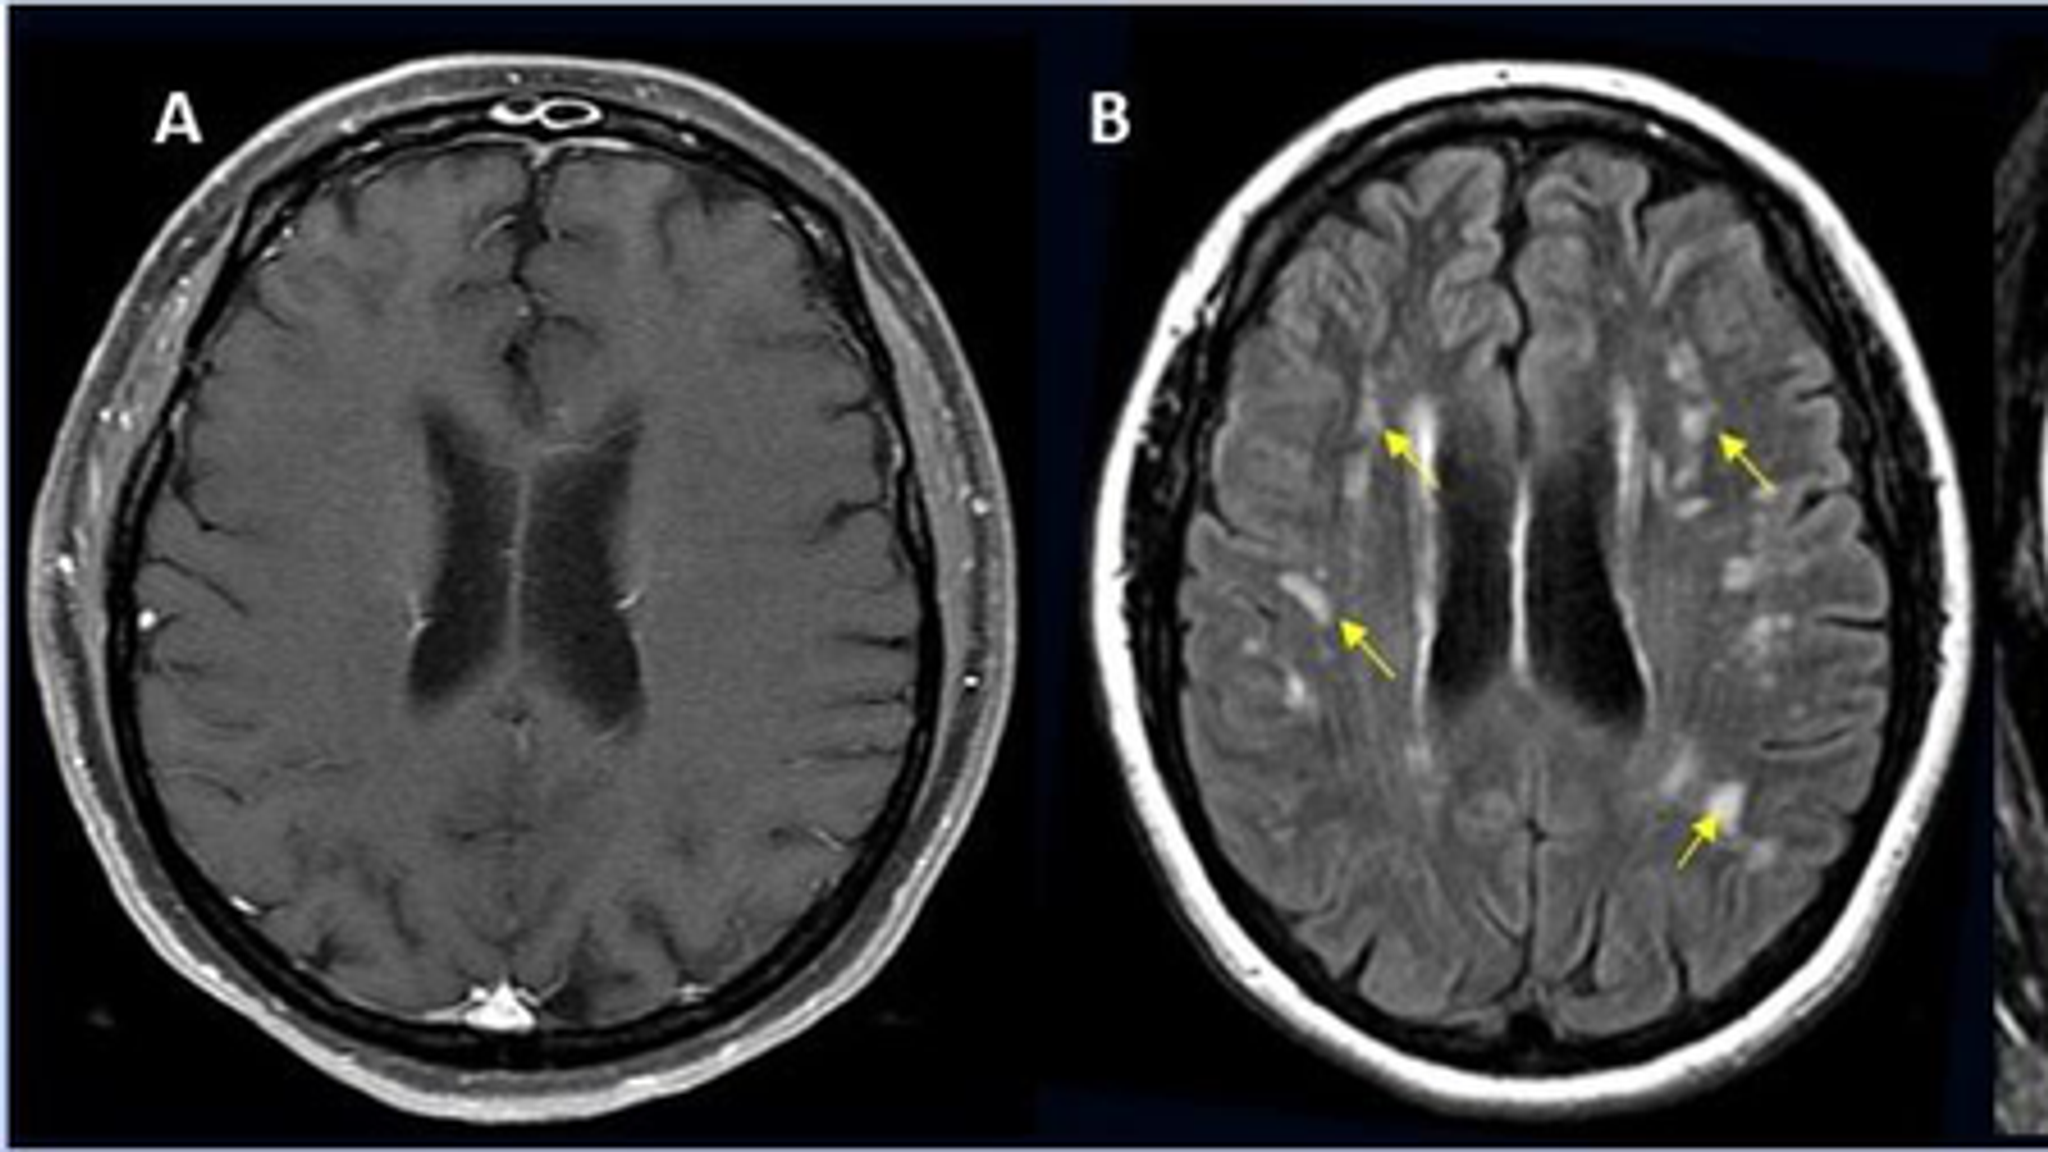

COVID19 and the Brain Neuropsychiatric Manifestations of Covid19 Covid Plaque On Brain Severe covid could cause markers of old age in the brain. Studies have suggested that during a bout of covid as many as 68% of people experience loss of smell and 44% lose their. Helena radbruch, a neuropathologist at the charité — berlin university medicine, and her colleagues looked at brain. Covid Plaque On Brain.

MRI Reveals Lasting Brain Changes in PostCOVID Patients Neuroscience Covid Plaque On Brain Severe covid could cause markers of old age in the brain. Helena radbruch, a neuropathologist at the charité — berlin university medicine, and her colleagues looked at brain. Studies have suggested that during a bout of covid as many as 68% of people experience loss of smell and 44% lose their. Covid Plaque On Brain.

BrainMRIFindingsInCOVID19 RSNA Covid Plaque On Brain Severe covid could cause markers of old age in the brain. Helena radbruch, a neuropathologist at the charité — berlin university medicine, and her colleagues looked at brain. Studies have suggested that during a bout of covid as many as 68% of people experience loss of smell and 44% lose their. Covid Plaque On Brain.

Unveiling COVID19’s Impact on the Brain Advanced MRI Reveals Key Changes Covid Plaque On Brain Severe covid could cause markers of old age in the brain. Helena radbruch, a neuropathologist at the charité — berlin university medicine, and her colleagues looked at brain. Studies have suggested that during a bout of covid as many as 68% of people experience loss of smell and 44% lose their. Covid Plaque On Brain.